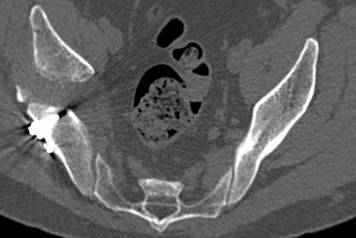

высылаю дополнительно сканы.

итак, второй вариант: высокий двухколонный с вовлечением КПС... Ни одно из основных повреждений не репонировано, кроме задней стенки. Скорее всего попытка реконструкции вертлуги сейчас будет очень травматичной и не очень эфективной, т.е. вероятный риск более значим, чем ожидаемая польза... Лучше подождать, и потом сразу эндопротез

подождать сколько, чего? такая дыра в задней колонне не закроется никогда.

потом эндопротез какой? в такой ситуации приходит на ум Burch-Schneider cage, в 35 лет, дальше что делать?